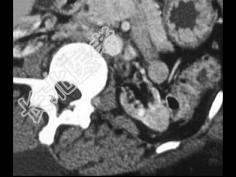

- 单项选择题患者长期透析,根据所提供的图像, 最可能的诊断是 ( )

A、肾囊肿出血

B、肾癌

C、转移癌

D、良性肿瘤

E、以上都不是